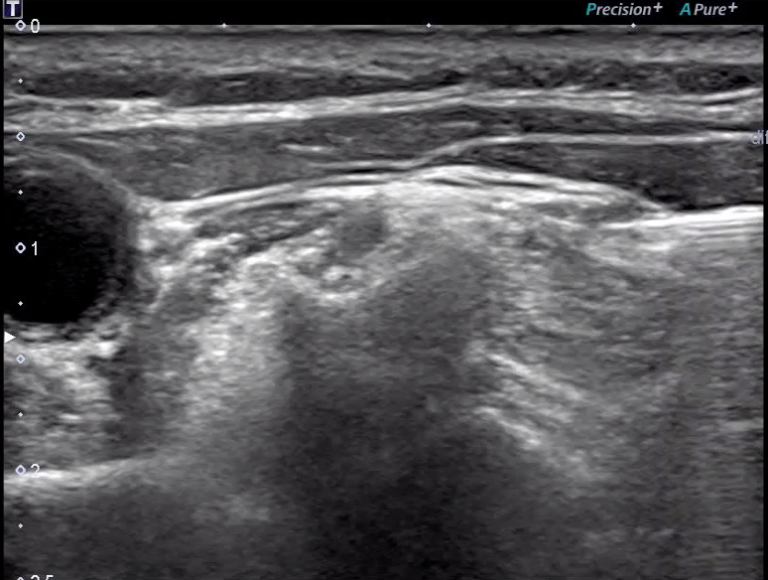

超音波治療實作錄影:第四頸椎

治療時,可以根據患者的症狀與影像結果,在超音波的導引下